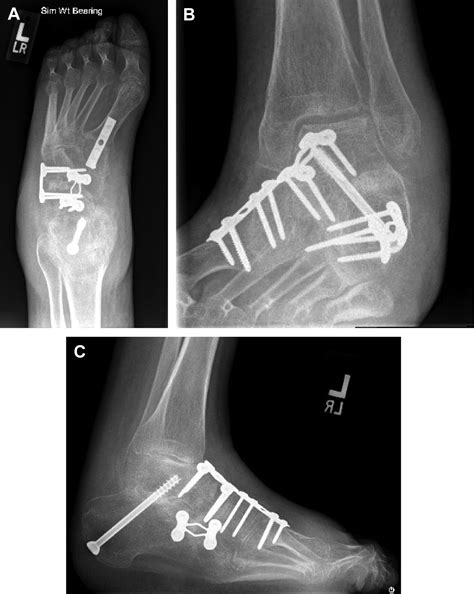

Ankle Fusion Procedures work by removing the damaged cartilage from the joint surfaces of the talus (the top bone of the foot) and the tibia (the shin bone). Once the cartilage is removed, the surgeon uses metal hardware, such as plates, screws, or rods, to hold these two bones together in a fixed position. Over the course of several months, the body naturally heals by bridging these bones with new bone tissue, creating a single, solid bone structure. The primary goal is to eliminate pain by preventing the grinding of bone-on-bone that occurs in advanced arthritis.

• Bone Healing: X-rays will be taken periodically to monitor the progress of the fusion. Weight-bearing is only permitted once there is radiographic evidence that the bones have securely fused.